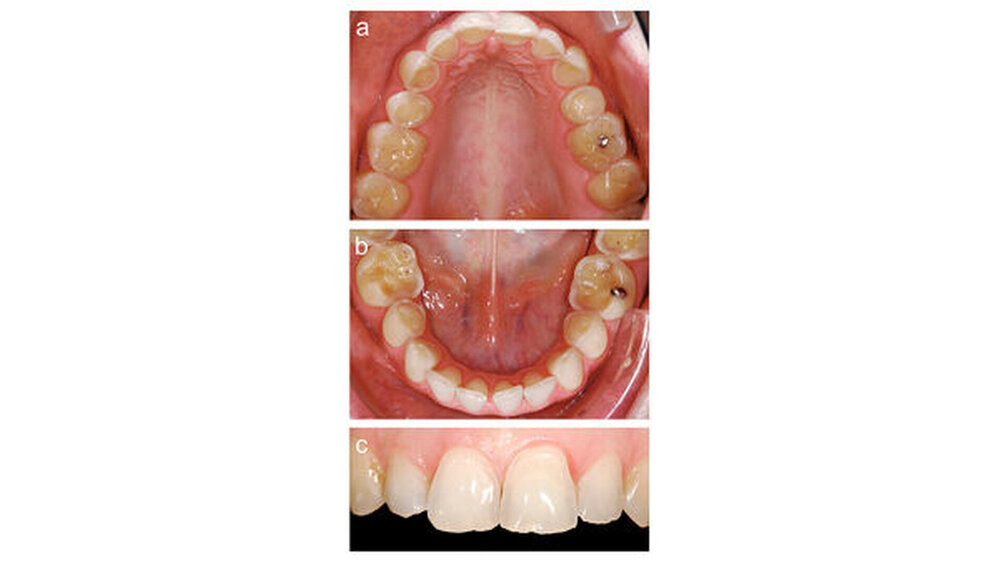

Eine 31 Jahre alte Patientin war von einem zahnärztlichen Kollegen zur weiteren Therapie überwiesen worden. Wie in Abbildung 1 zu erkennen, wies sie an allen Zähnen erosive Defekte auf, die sich bevorzugt auf den Okklusal- und Palatinalflächen im Seitenzahngebiet manifestiert hatten. Im Frontzahngebiet lagen sowohl palatinal als auch inzisal-bukkal erosiv veränderte Zahnoberflächen vor. Die Patientin gab an, unter gastroösophagealem Reflux zu leiden, der medikamentös mit H2-Blockern von ihrem Hausarzt behandelt und kontrolliert wurde. Sie litt unter Hypersensibilitäten der Seitenzähne. Zudem störte sie das Erscheinungsbild ihrer Oberkieferfrontzähne.